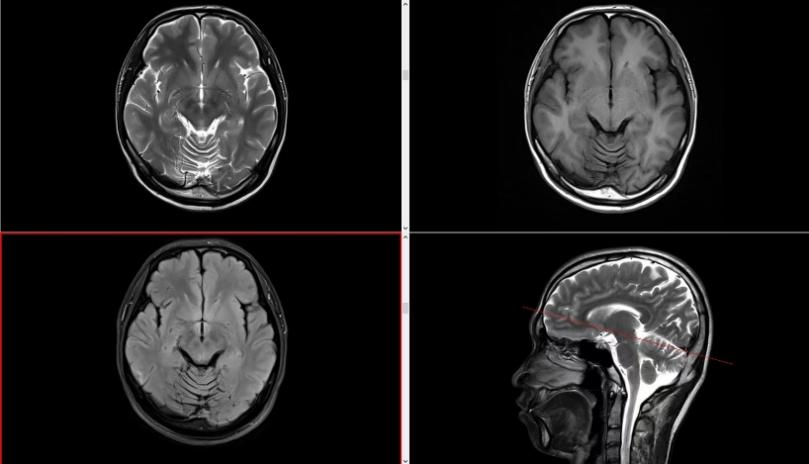

PET CT检查项目在医学诊断中具有广泛的应用价值,包括肿瘤早期诊断及良恶性鉴别和疗效评估、评估心血管病变的程度及范围,在癫痫病灶定位、神经系统病变诊断和身体局部病变检查等方面也具有一定的应用价值。

我们的服务项目涵盖了全身各部位的影像检查,包括但不限于:头部、颈部、胸部、腹部、盆腔、四肢等部位的CT、MRI、DR等检查。我们还提供特殊的影像检查服务,如血管造影、MR多功能成像等。例如:

磁共振检查: